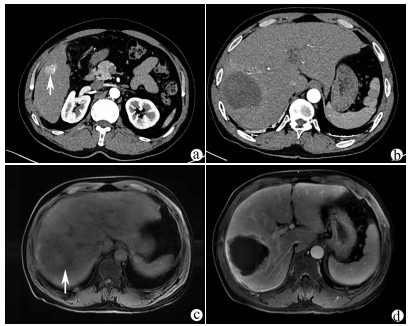

目的  探讨肝脏三维可视化重建技术在儿童复杂肝母细胞瘤肝切除术中的应用价值。  方法  回顾分析2018年1月—2020年10月于火箭军特色医学中心实施了以根治性切除为目的的肝肿瘤切除术的30例肝母细胞瘤患儿的临床资料,根据术前是否行肝脏三维重建(IQQA-Liver系统)将所有患儿分为三维重建组(n=15)和对照组(n=15),比较2组患儿围手术期临床参数以及短期预后和随访情况。符合正态分布的计量资料2组间比较采用独立样本t检验,不符合正态分布的计量资料2组间比较采用Mann-whitney U检验。计数资料2组间比较采用Fisher确切概率法。  结果  三维重建组较对照组平均年龄更大[(55.7±10.2)月vs (28.2± 2.7)月]、POSTTEXT Ⅲ/Ⅵ期(12例vs 5例)和肝静脉或下腔静脉受累者(11例vs 3例)更多,差异均有统计学意义(P值均<0.05)。所有患儿均顺利完成手术,2组在出血量、手术时间、肝门阻断次数/时间、行肝段及部分肝切除例数方面,差异均无统计学意义(P值均>0.05)。术后中位随访时间9.5个月,三维重建组2例复发,分别于术后10个月和12个月确诊,目前继续化疗中;对照组4例复发,高于三维重建组(P=0.651),其中2例在术后7个月复发接受肝移植存活至今,另有2例复发后短期内死亡。  结论  三维可视化重建技术有助于更安全精准实施复杂儿童肝母细胞瘤肝切除术,尤其是可以使部分POSTTEXT Ⅲ/Ⅵ期患者安全实施扩大肝切除,从而避免行肝移植。

摘要(1294) HTML (489) PDF (3321KB)(55)

摘要:

目的  探讨高原地区体外肝切除联合自体肝移植术治疗终末期肝泡型包虫病的术后并发症并探讨防治策略。  方法  收集青海省人民医院2013年1月— 2019年3月接受自体肝移植术的11例终末期肝泡型包虫病患者的手术资料及随访资料,对术中及术后情况进行分析。  结果  11例患者均成功行自体肝移植术,无术中死亡,其中2例(18.18%)行半离体肝切除,9例(81.82%)行全离体肝切除。肝后下腔静脉重建方式中,采用自体大隐静脉进行重建者2例(18.18%),采用人造血管重建者4例(36.36%),5例(45.45%)保留自体肝后下腔静脉。胆道重建方式中,8例(72.73%)行胆肠吻合术,3例(27.27%)行胆管端端吻合术。11例患者的术后并发症主要有出血2例(18.18%);胆汁漏、腹腔感染4例(36.36%),胆肠吻合口狭窄1例(9.09%), 血栓2例(18.18%),肺部感染、胸腔积液2例(18.18%);包虫复发1例(9.09%)。11例患者发生围术期死亡2例(18.18%),其余9例(81.82%)患者均好转出院。  结论  出血、胆道并发症和感染是造成高原地区自体肝移植患者死亡的主要原因,精准把握手术适应证、术前仔细多学科评估、术中精湛的操作、外科技术流程的标准化及精细的围术期管理是降低自体肝移植术围术期病死率、避免和减少术后并发症以及使患者获得长期良好生存的关键。